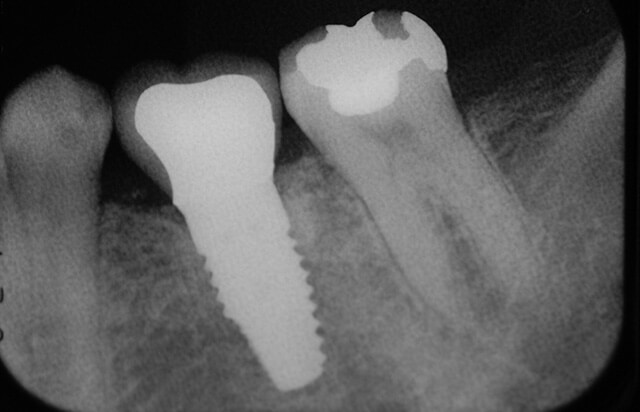

同日の術前とインプラント埋入後のレントゲン写真です。早期埋入になりますが、理想的に埋入されています。

治療後

抜歯からおよそ10ヶ月でインプラント治療による咬合が回復されました。補綴物(被せ物)は、セラミックを装着しています。抜歯後2ヶ月の写真と比較して、補綴物周囲の歯肉は歯周外科処置によりブラッシングしやすい厚みのある歯肉に改善されています。レントゲン像からはインプラント周囲の歯槽骨が平坦で、全く吸収が無い理想的な骨の状態が確認できます。